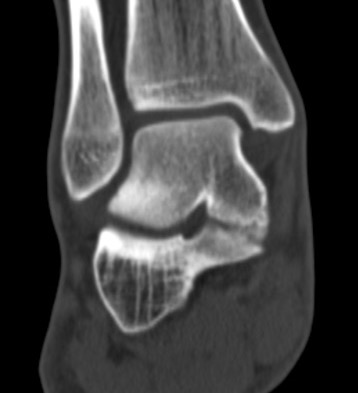

CT

TC coalition middle facet

Complete synostosis of the medial TC joint with OA of the posterior subtalar joint